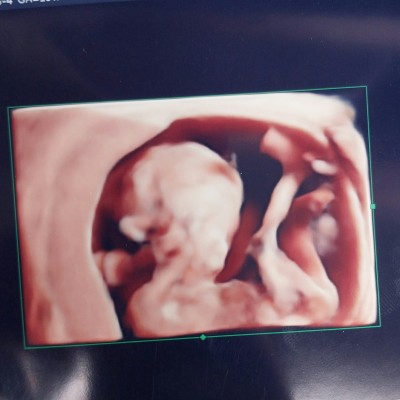

Cinsiyet tahmini lutfennnn

Resimli kizlar tahminde bulunununuz anlayanlat

15+6

Ben kıza benzettim oğrendinizmi

kiz annesi

kız gibi canım

Bu haftada ve bu pozisyonda belli olmasi lazimdi ben 15+ 5 günlükken öğrendim sizinki kiz bence bacak arasindan sarkan bisey göremedim ama tahmin ediyorum tabiki de bu sekilde bizim bilmemiz mümkün değil hayırlısı olsun :)

Canim erkek olsaydi bu pozisyonda pipisi cok cok yüksek ihtimalle görünecekti yani belli ederdi kendini kiz olma ihtimali daha yüksek Rabbim hayırlı evlat eylesin insallah :)

Kız gibi duruyor bacak arası bariz belli

Kız bebek bence